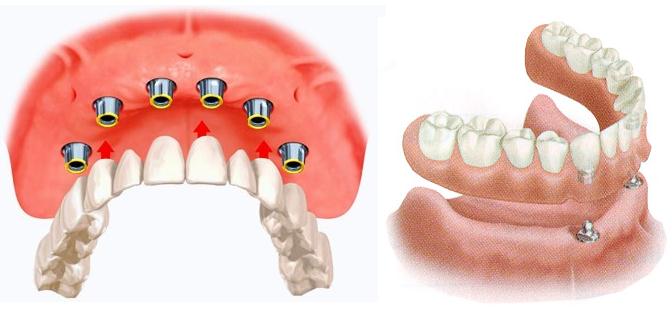

- Протезы на имплантатах, которые чаще всего используют в случае восстановления зубного ряда полностью. Они требуют установки всего 4-х имплантатов на передней части челюсти. Подобный вариант протезирования подойдёт тем, кому не по карману дорогие мостовидные протезы. Такие конструкции не натирают десны, не смещаются в ротовой полсти и очень надежно фиксируются.

- В первую очередь, проводят вживление имплантатов: на верхнюю челюсть – три имплантата, а на нижнюю – два. Однако необходимо помнить, что, в случае минимального количества имплантатов, протез станет немного балансировать, смещаясь в незакрепленных отделах. Поэтому чем больше установлено имплантатов, тем более надежно протез будет зафиксирован во рту.

- После приживления имплантатов проводят установку абатментов (промежуточного звена между зубной коронкой и имплантатом).

- И, наконец, осуществляют крепление протеза с помощью шаровидного замка, специальных винтов, балки либо цемента.